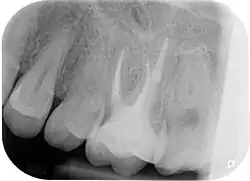

Zur Beurteilung des Erfolges einer Wurzelkanalbehandlung werden klinische Beschwerden, wie Schmerzen, Schwellungen oder Fistelgänge sowie der röntgenologische Befund herangezogen. Oft sind trotz endodontischer Infektion keine klinischen Beschwerden vorhanden, weshalb gerade die röntgenologische Kontrolle Hauptkriterium für die Beurteilung ist.[10] Neben der vorhandenen Wurzelfüllung und Veränderungen in der Wurzelphysiognomie (Resorptionen) wird vor allem der Zustand des periapikalen Gewebes begutachtet und auf das Vorhandensein einer Parodontitis apikalis oder einer radikulären Zyste geprüft.

Wenn eine Verbesserung des Ausgangszustandes und eine Beseitigung der möglichen Ursachen nicht zu erwarten sind oder die Erhaltung des Zahns fragwürdig ist, ist von einer Revision abzusehen. Ebenso müssen nicht-endodontische Ursachen der Erkrankung vor einem Eingriff ausgeschlossen werden.[1] Nach Strindberg et al. wird der endodontische Misserfolg nach einer ausreichenden Heilungszeit von vier Jahren mit dem Vorhandensein einer residuellen, persistierenden oder progredienten röntgenologischen Aufhellung (Dunkler Punkt an der Wurzelspitze im Röntgenbild) und/oder mit dem Vorhandensein klinischer Beschwerden jeglicher Form definiert.[18]